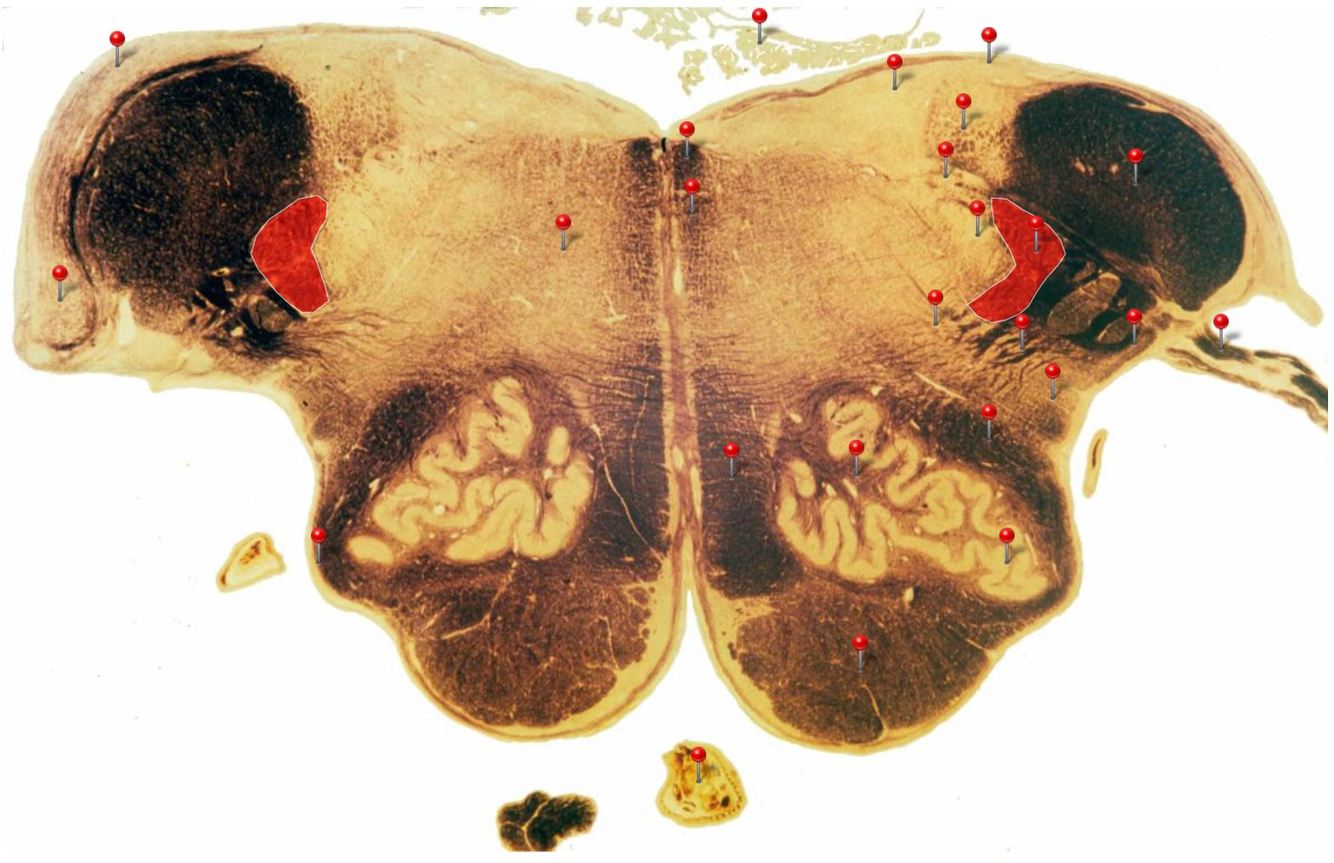

11

Q

Corticospinal Tract

Rostral Medulla

Controls precision and speed of skilled movements involving the distal muscles of the contralateral limbs, particularly those of the hands and fingers

12

Nucleus Ambiguus

Neurons supply the muscles of the pharynx, larynx, upper oesophagus and heart

13

Basilar Artery

Provides blood supply to much of the cerebellum, pons, midbrain and posterior thalamus as well as part of the temporal (inferior surface) and occipital (medial and inferior surfaces) lobes

14

Olives

Elevations formed by the inferior olivary nuclei which integrate information from a variety of sources before relaying it to the cerebellum

15

Rubrospinal Tract

Assists in the control of movements of the hands and fingers

16

Medial Vestibular Nucleus

Process inputs from vestibular receptors of the inner ear and are involved in the regulation of posture and the coordination of head and eye movements

17

Spinal Trigeminal Tract

Transmits somatosensory (crude touch, pain and temperature) inputs from the Trigeminal nerve (CN V) through the midpons and medulla to the spinal trigeminal nucleus.

18

Ventral Cochlear Nuclei

One of the relay nuclei for the auditory fibres of the vestibulocochlear nerve (CN VIII) and functions to modify inputs to the higher auditory structures

19

Medial Longitudinal Fasciculus

Pathway through which eye movements are coordinated with changes in head position

20

Dorsal Cochlear Nuclei

One of the relay nuclei for auditory fibres of the vestibulocochlear nerve (CN VIII) and functions to modify inputs to the higher auditory structures

21

Inferior Olivary Nucleus

Plays an important role in the learning of new motor skills

22

Solitary Nucleus

Processes visceral afferent (GVA and SVA [taste]) inputs from CN VII, IX and X and relays them to the reticular formation and visceral efferent nuclei

23

Spinal Trigeminal Nuclei

Processes sensory inputs, particularly pain and temperature, from the head and neck and relays them to the ventral posteromedial nucleus of the thalamus

24

Inferior Vestibular Nucleus

Plays a role in the maintenance of balance and the coordination of eye and head movements

25

Medial Lemniscus Rostral Medulla Transmits sensations of **discriminative touch, vibration, proprioception** an **stereognosis** from the *gracile* and *cuneate nuclei* to the *ventral posterior nuclei of the thalamus*

26

Ventral Spinocerebellar Tract Rostral Medulla Provides feedback to the cerebellum concerning motor activity (including reflexes) in the lumbosacral levels of the spinal cord

27

Glossopharyngeal Nerve (CN IX) Rostral Medulla Transmits taste and tactile sensation from the posterior part of the tongue, pharynx and ear, and visceral sensation from the chemo- and baroreceptors of the carotid body and sinus (also supplies efferent fibres to the otic ganglion and stylopharyngeus m.)

28

Inferior Cerebellar Peduncle Rostral Medulla Formed by pathways passing in both directions between the medulla and cerebellum

29

Tectospinal Tract Rostral Medulla Function in humans not precisely determined; thought to mediate reflex movements of head in response to visual and perhaps auditory stimuli

30

Olivocerebellar Tract Rostral Medulla Transmits information from inferior olivary nucleus to the *contralateral* cerebellum, where it forms the **climbing fibres**

31

Lateral Vestibular Nucleus Rostral Medulla Contains cell bodies of the (lateral) vestibulospinal tract which regulates the activity of **axial** and **proximal** limb muscles in order to **maintain balance and posture**